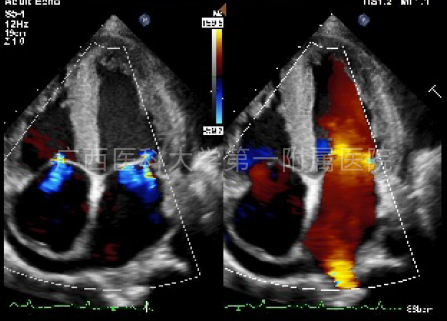

心脏超声心动图提示:双侧心房增大,心室不大,室间隔及左室后壁增厚,心肌回声光点稍呈颗粒状增强